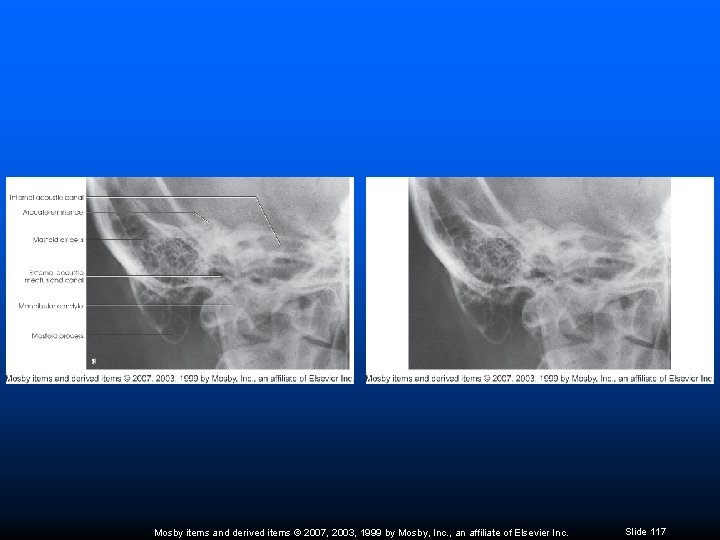

Axiolateral Oblique Temporal Bone (Stenvers) Petromastoid portion in profile Lateral border of skull to lateral border of orbit Petrous ridge extended to a point about two thirds up lateral border of orbit Mosby items and derived items © 2007, 2003, 1999 by Mosby, Inc. , an affiliate of Elsevier Inc. Slide 115

Axiolateral Oblique Temporal Bone (Stenvers) Mastoid process in profile below cranium Posterior margin of mandibular ramus superimposing lateral border of C-spine Mandibular condyle projecting over atlas near petrosa Close beam restriction Mosby items and derived items © 2007, 2003, 1999 by Mosby, Inc. , an affiliate of Elsevier Inc. Slide 116

Mosby items and derived items © 2007, 2003, 1999 by Mosby, Inc. , an affiliate of Elsevier Inc. Slide 117

Axiolateral Oblique Temporal Bone (Arcelin) Petromastoid portion in profile Lateral border of skull to lateral border of orbit Petrous ridge lying horizontal about two thirds up lateral border of orbit Mosby items and derived items © 2007, 2003, 1999 by Mosby, Inc. , an affiliate of Elsevier Inc. Slide 118

Axiolateral Oblique Temporal Bone (Arcelin) Mastoid process in profile below cranium Posterior margin of mandibular ramus superimposing lateral border of C-spine Mandibular condyle projecting over atlas near petrosa Close beam restriction Mosby items and derived items © 2007, 2003, 1999 by Mosby, Inc. , an affiliate of Elsevier Inc. Slide 119